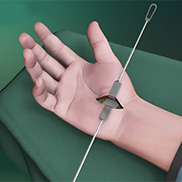

Know More Launch Movie - Carpal Tunnel Release Surgery

Carpal tunnel syndrome is a common, painful, progressive condition that is caused by the compression of the median nerve at the wrist area.